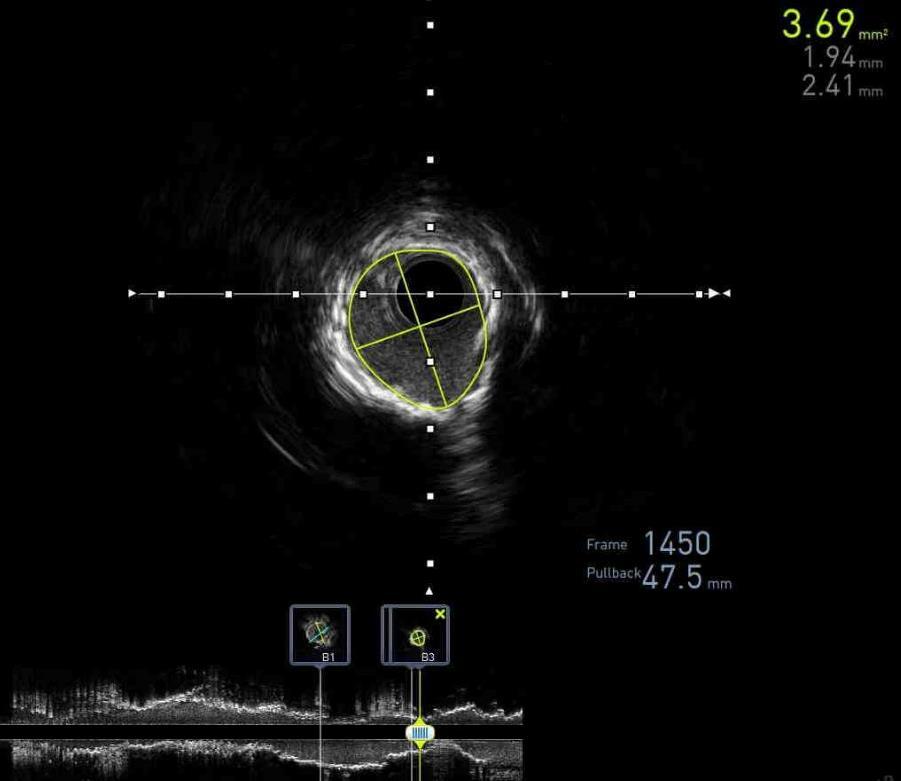

IN-STENT THROMBOSIS THRICE IN 30 DAYS

42

43

Luka Katic1, Hammad Sheikh1, Alexander Silverman1 , Ankita Gore1, Nitin Barman1 , Amir Ahmadi1

1Mount Sinai Morningside-West Hospitals, Icahn School of Medicine at Mount Sinai, New York, NY, United States

Presented at the Annual Mount Sinai Fuster Heart Research Forum that was held in New York, New York, United States on March 15, 2024.